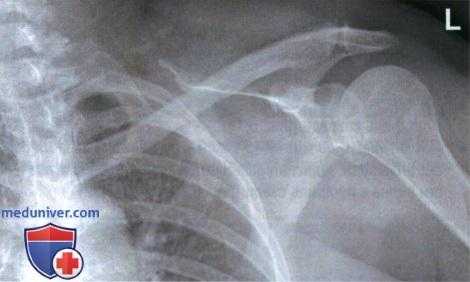

РИСУНОК 3 Рентгенограмма лопатки в ПЗ проекции без отведения плеча. РИСУНОК 4 Рентгенограмма лопатки в ПЗ проекции с недостаточной ретракцией плечевого сустава. РИСУНОК 5 Рентгенограмма лопатки в ПЗ проекции: перелом.

а) Отведение плечевой кости на 90° относительно туловища. В 80% случаев переломы лопатки возникают в ее теле или шейке. Шейка лопатки лучше всего визуализируется на рентгенограммах в ПЗ проекции, поскольку в боковой проекции она видна в торец. При подозрении на перелом тела лопатки рентгенография в боковой проекции позволяет оценить смещение отломков в передне-заднем направлении. Чтобы лучше отобразить тело лопатки, следует расположить ее длинную ось параллельно длинной оси ПИ отведя плечевую кость на 90° относительно туловища (рис. 3 и 4). В таком положении лопатка скользит вперед вдоль грудной клетки, суставная впадина лопатки слегка наклоняется вверх и длинная ось тела лопатки становится параллельна ПИ (см. рис. 1).

д) Перелом проксимального отдела плечевой кости. При переломе проксимального отдела плечевой кости на рентгенограмме плечевого сустава в косой ЗП проекции будет отмечаться наложение головки плечевой кости на суставную впадину лопатки, однако диафиз плечевой кости будет визуализироваться спереди или сзади тела лопатки (рис. 8). При подозрении на такой перелом важно, чтобы лопатка была правильно отображена в виде буквы Y, чтобы можно было оценить ее положение относительно диафиза плечевой кости. На рис. 9 показана еще одна рентгенограмма того же пациента. Сравните правильность отображения лопатки в виде буквы Y и положение головки и диафиза плечевой кости.